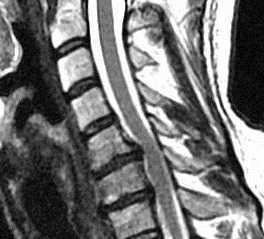

Комплекс дегенеративных изменений позвоночника может приводить к сужению позвоночного канала и/или бокового кармана, видимое при КТ и МРТ позвоночника. Часто это состояние обозначают термином “спондилёз”. Этому способствует также врождённая узость канала вследствие коротких корней дуг.

МРТ шейного отдела позвоночника. Стеноз позвоночного канала . Сагиттальная Т2-взвешенная МРТ.